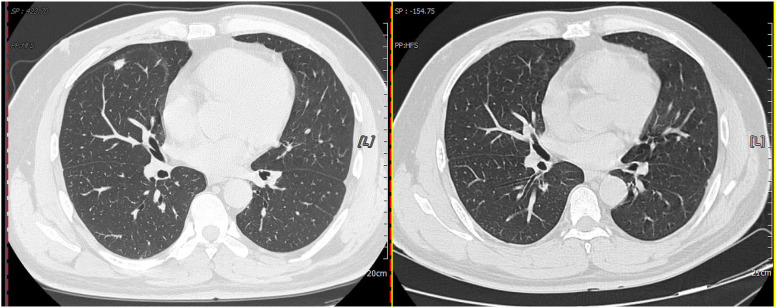

Results: Most patients in the PC group are male (59.6%), with an average age of 49.4 years. Most of the patients have no underlying disease (51.9%). Diabetes and hypertension are the most common comorbidities. Most patients (53.8%) are asymptomatic. Cough and sputum are the most frequent clinical symptoms, followed by fever and chest distress. Nodules and exudative consolidation are the most common imaging findings, and the culture positivity rate is 25%. Forty patients are positive according to the BALF GXM test, for a positivity rate of 83.3% and a negative predictive value of 91.8%. Moreover, 39 patients are positive according to the serum GXM test, for a positivity rate of 81.3% and a negative predictive value of 90.9%. The positivity rate for serum plus BALF is 95.8%. There is no significant difference (P > 0.05) in diagnostic value between BALF and serum GXM tests for PC. GXM positivity rates differ significantly among paired BALF, serum, and BALF plus serum groups (P < 0.05).

Abstract Image